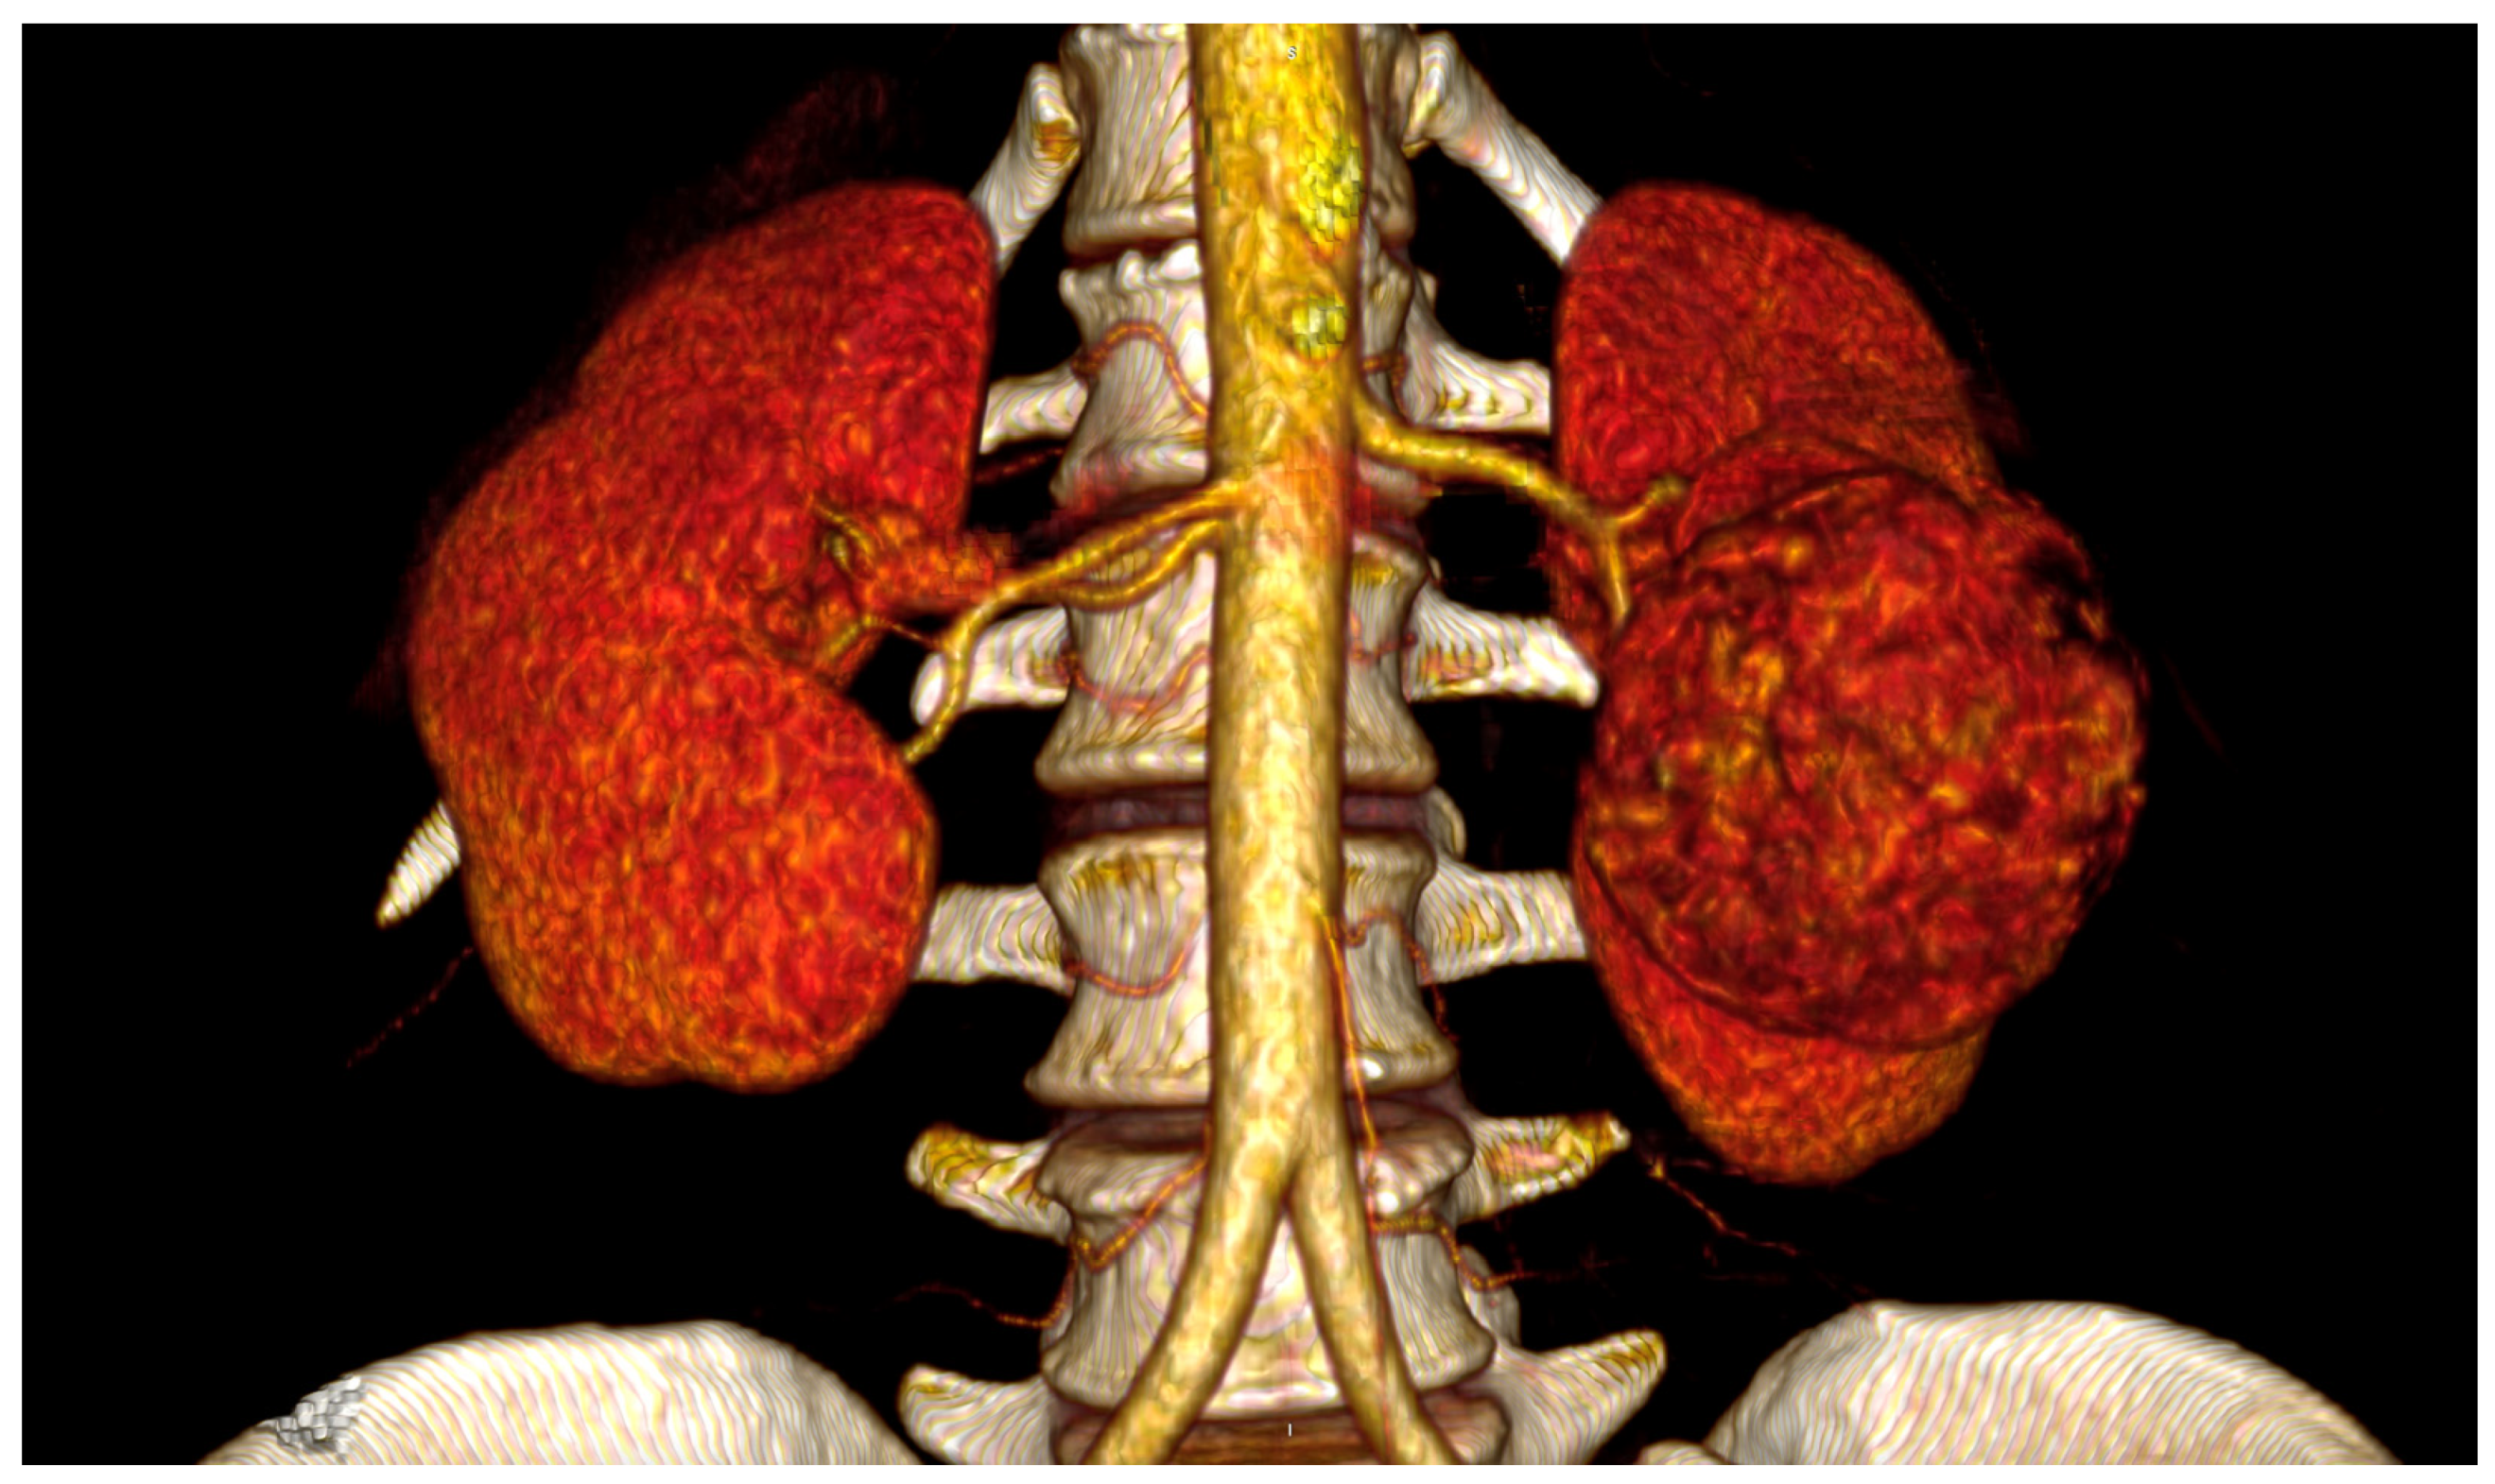

The spatial relationships between CT, SMA and RA are extremely variable in physiological conditions, and clearly influenced by different pathological conditions. Regarding the common origin from the aorta, both CT and SMA arise, in the majority of cases, from the anterior wall, whereas the RA originate from the lateral or anterolateral wall of the aorta. In particular, the LRA originates from the anterolateral wall in 52%, from the lateral wall in 45% and from the posterior wall of the aorta in 3% of cases [5]. Cadaveric studies have shown great variability of the distance between the ostia of origin of CT, SMA, and RA, generally not exceeding the value of 10 mm [5,6,7,8], varying around an average of 6 mm between the SMA and the LRA [9,10,11] in studies based on in-vivo computed tomography scans (Figure 1).

Figure 1. Three-dimensional reconstruction of vascular anatomy spatial relationships on computed tomography scan with intravenous contrast: the patient had combined SMA and splenic artery injuries during laparoscopic left radical nephrectomy for a large renal cell carcinoma with periaortic tissue involvement.